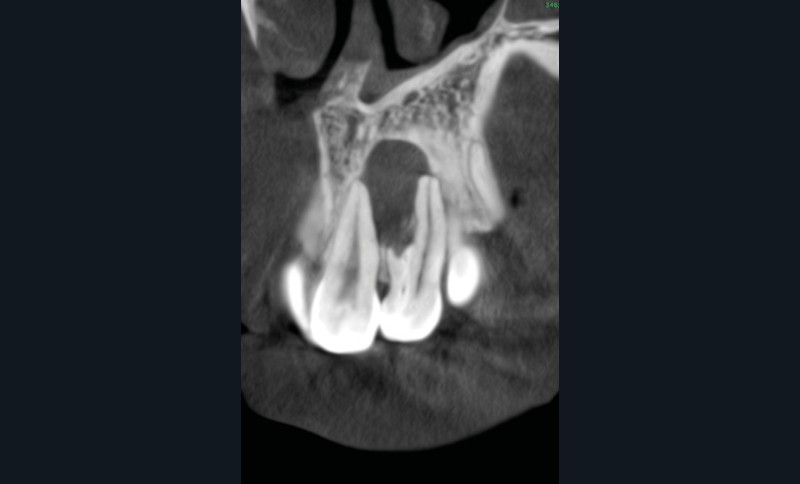

L’examen rétro-alvéolaire montre une anatomie atypique évoquant une invagination de l’émail communiquant avec le parodonte profond (dens invaginatus type III a selon Oehlers) [2] (fig. 1). L’analyse CBCT permet de mieux visualiser l’étendue de la lésion et l’anatomie radiculaire de la 22. L’invagination et le canal ont deux trajets indépendants sur toute leur longueur (fig. 2 et fig. 3a et b).